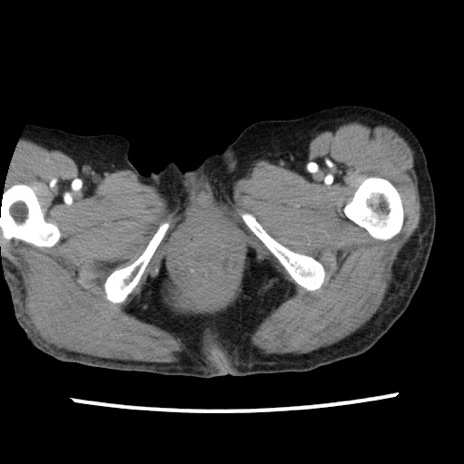

症例1(横断像)

症例

【症例】80歳代女性

【主訴】腹痛

【現病歴】8時間前から腹痛あり来院。

【既往歴】糖尿病、脂質異常症、子宮体癌にて子宮全摘術

【身体所見】意識清明・会話良好だが腹痛で苦悶様、全腹部にわたって反跳痛と圧痛あり

【データ】WBC 13600、CRP 0.14、LDH 224、CK 90